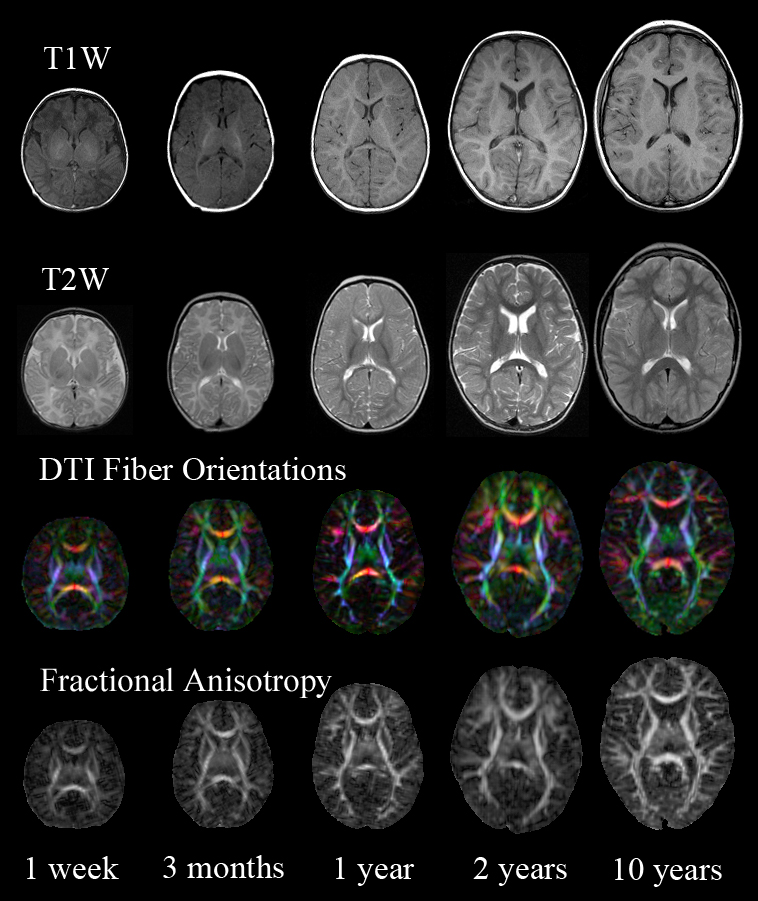

Imaging Data

1. Acquisition & Storage

2. Visualisation:

Imaging Browser, BrainBrowser3. Quality Control:

Imaging Browser

Imaging Quality Control

BrainBrowser

..a set of web-based 3D visualization tools primarily used for viewing neurological data i.e. MRI scans.

It allows for real-time manipulation and analysis of 3D neuroimaging data through any modern web browser. TRY ME!

BrainBrowser - 3D Surface Viewer